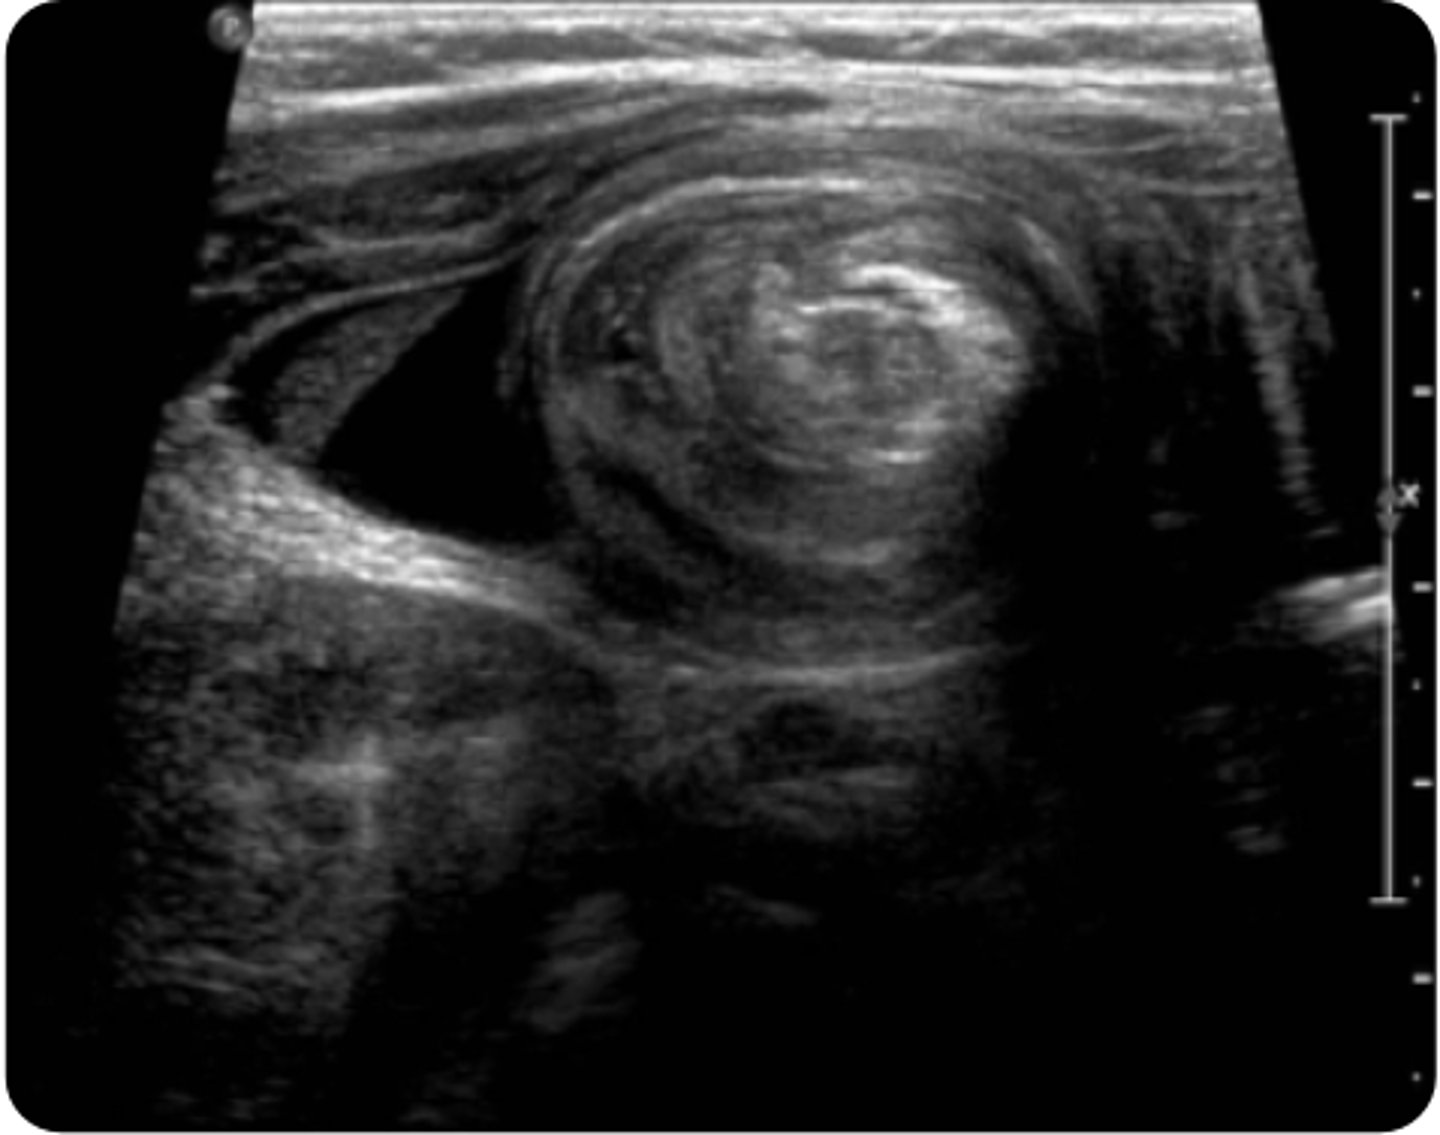

relapsing-remitting pain episodes

**intussusception

An 18-month-old boy presents to the emergency department with his parents for what they believe to be abdominal pain for the past 2 hours. The patient has been experiencing episodes of inconsolable crying that last around 15 minutes. During these times, the patient draws his legs up to his abdomen and cries. Between crying episodes, the patient appears lethargic. He also vomited twice in the car on the way to the hospital. Of note, the patient’s father was ill 3 days ago with vomiting and diarrhea. The patient’s vital signs are a blood pressure of 100/60 mm Hg, a heart rate of 110 bpm, a respiratory rate of 18 breaths per minute, an oxygen saturation of 96%, and a temperature of 100.6°F. Upon physical examination, the lungs are clear to auscultation and a cardiac exam reveals a regular rate and rhythm with no murmurs, gallops, or rubs. An ENT examination is within normal limits. Upon abdominal examination, a sausage-shaped mass is palpable in the right upper quadrant. A genital examination reveals grossly bloody stool in the diaper. An abdominal ultrasound is obtained and is shown above. Which history, clinical manifestation, or exam finding is most likely associated with the suspected diagnosis?

AFamily history of gastroenteritis

BFever

CLethargy

DRelapsing-remitting pain episodes